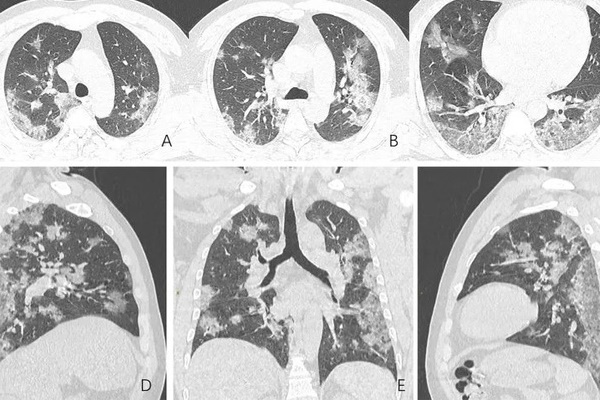

Hình ảnh chụp cắt lớp vi tính của phổi bệnh nhân 44 tuổi nhiễm Covid-19 tại Vũ Hán - có thể thấy rõ những đốm trắng hình thành và lan rộng. Ảnh: Newsweek.

Trong hình ảnh chụp CT của bệnh nhân 44 tuổi ở Vũ Hán, có thể thấy rõ các mảng trắng hình thành trên phổi của người này. Thông thường đây được coi là một dấu hiệu bất thường mà các bác sĩ X-quang gọi là "tổn thương kính mờ" - khi một phần khí trong phế nang bị thay thế bởi dịch tiết hoặc dịch thấm, hoặc tổ chức xơ kèm dày, hoặc phế nang bị xẹp.

"Khi điều này xảy ra, bệnh nhân sẽ cảm thấy rất khó thở, nồng độ oxy thấp, ho và có các triệu chứng hô hấp khác... Phổi bình thường trên hình chụp CT sẽ có màu đen hoặc xám đen. Các khu vực bất thường sẽ có màu trắng", ông Callahan cho biết.